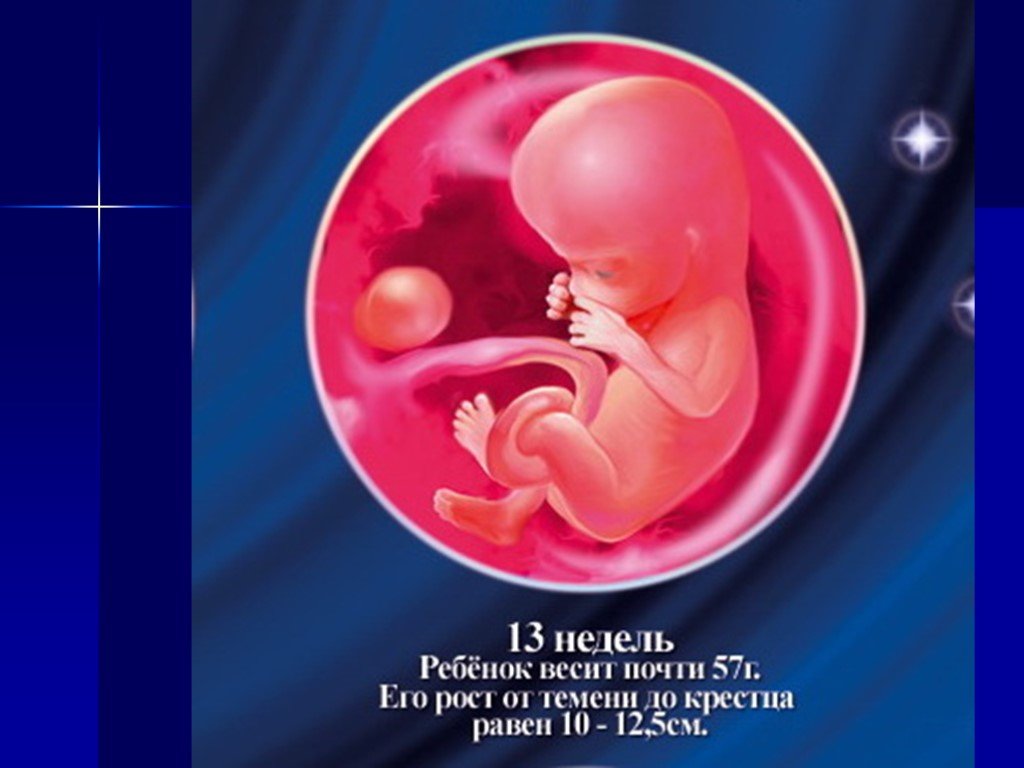

Удивительные фотографии эмбриона на 8 неделе беременности